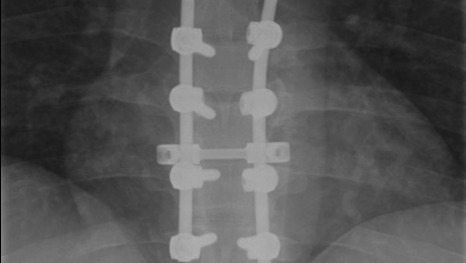

This year marks the 10th anniversary of a severe snowboarding accident that very nearly left me paralyzed. I had hit a patch of ice while on a double diamond run, lost control, went airborne as I slid off the trail, and struck a tree backwards. The impact fractured two thoracic vertebrae, fractured a rib, cracked my thorax, caused an elbow injury, and lots of internal swelling. Because of the severity of the fractures, I had to have a spinal fusion surgery to ensure the vertebrae did not damage my spinal cord, and so, for the rest of my life I will have 4 vertebrae permanently fused together with 3 titanium rods and 8 screws.